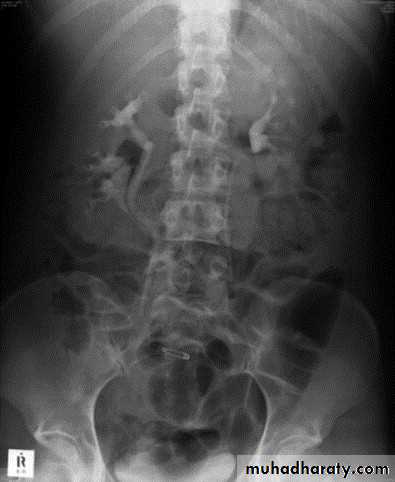

Mega ureter :

Unilateral or bilateral dilatation of the ureter with no evidence of organic obstruction. o Cause – unknown

Retrocaval ureter :

The middle third of right ureter curve medially behind the IVC , then laterally to regain it’s normal position , this lead to obstruction of upper third of ureter.